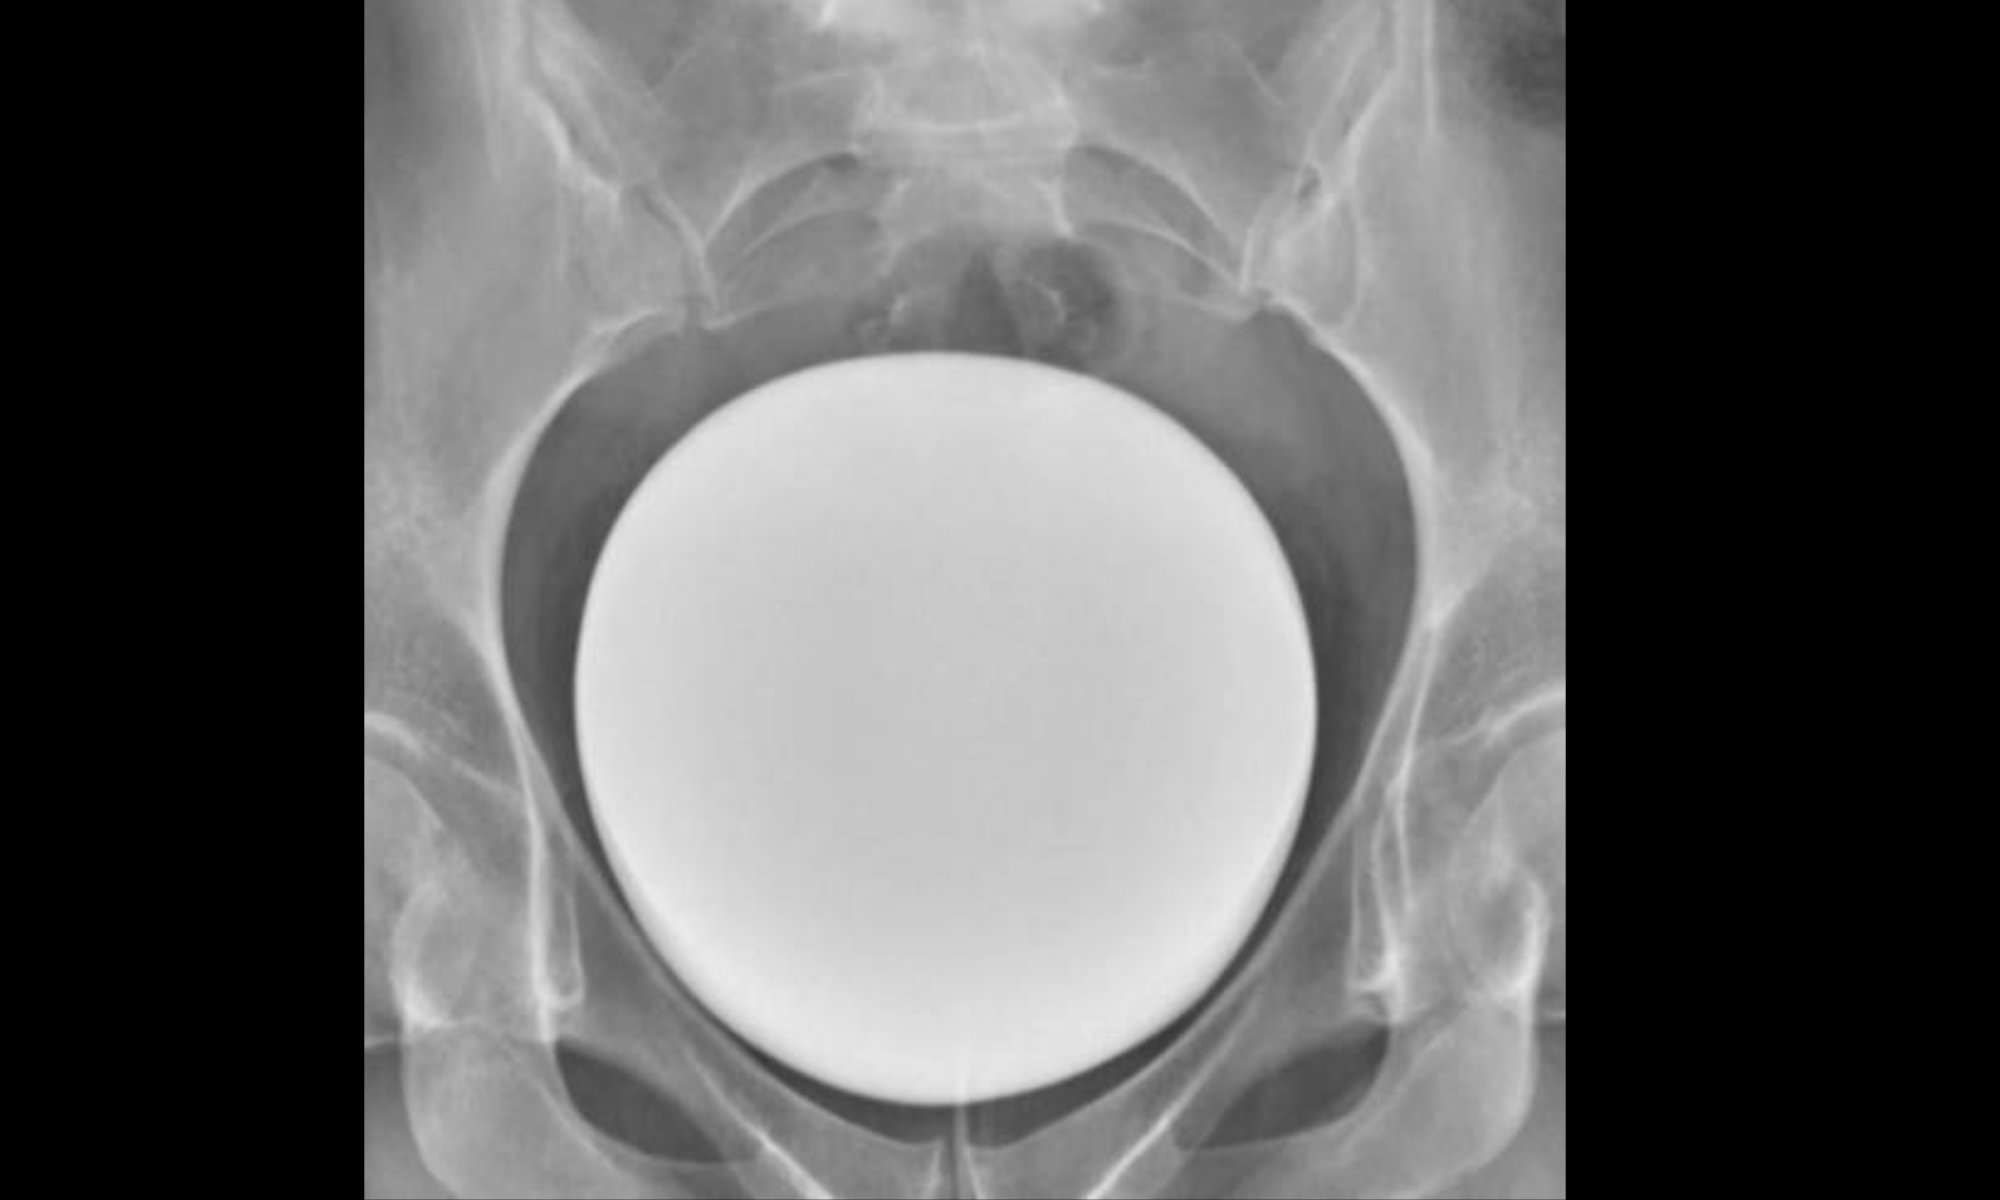

Cet examen permet d’étudier la paroi vésicale, le fonctionnement de la vessie et explore les troubles de l’évacuation des urines (miction).

Après une toilette soigneuse des organes génitaux externes, le radiologue pose une sonde urinaire à usage unique qui permet le remplissage de la vessie par l’intermédiaire d’une perfusion.

Le manipulateur effectue des clichés de vessie pendant le remplissage de celle-ci et des clichés pendant que vous urinez (clichés mictionnels).